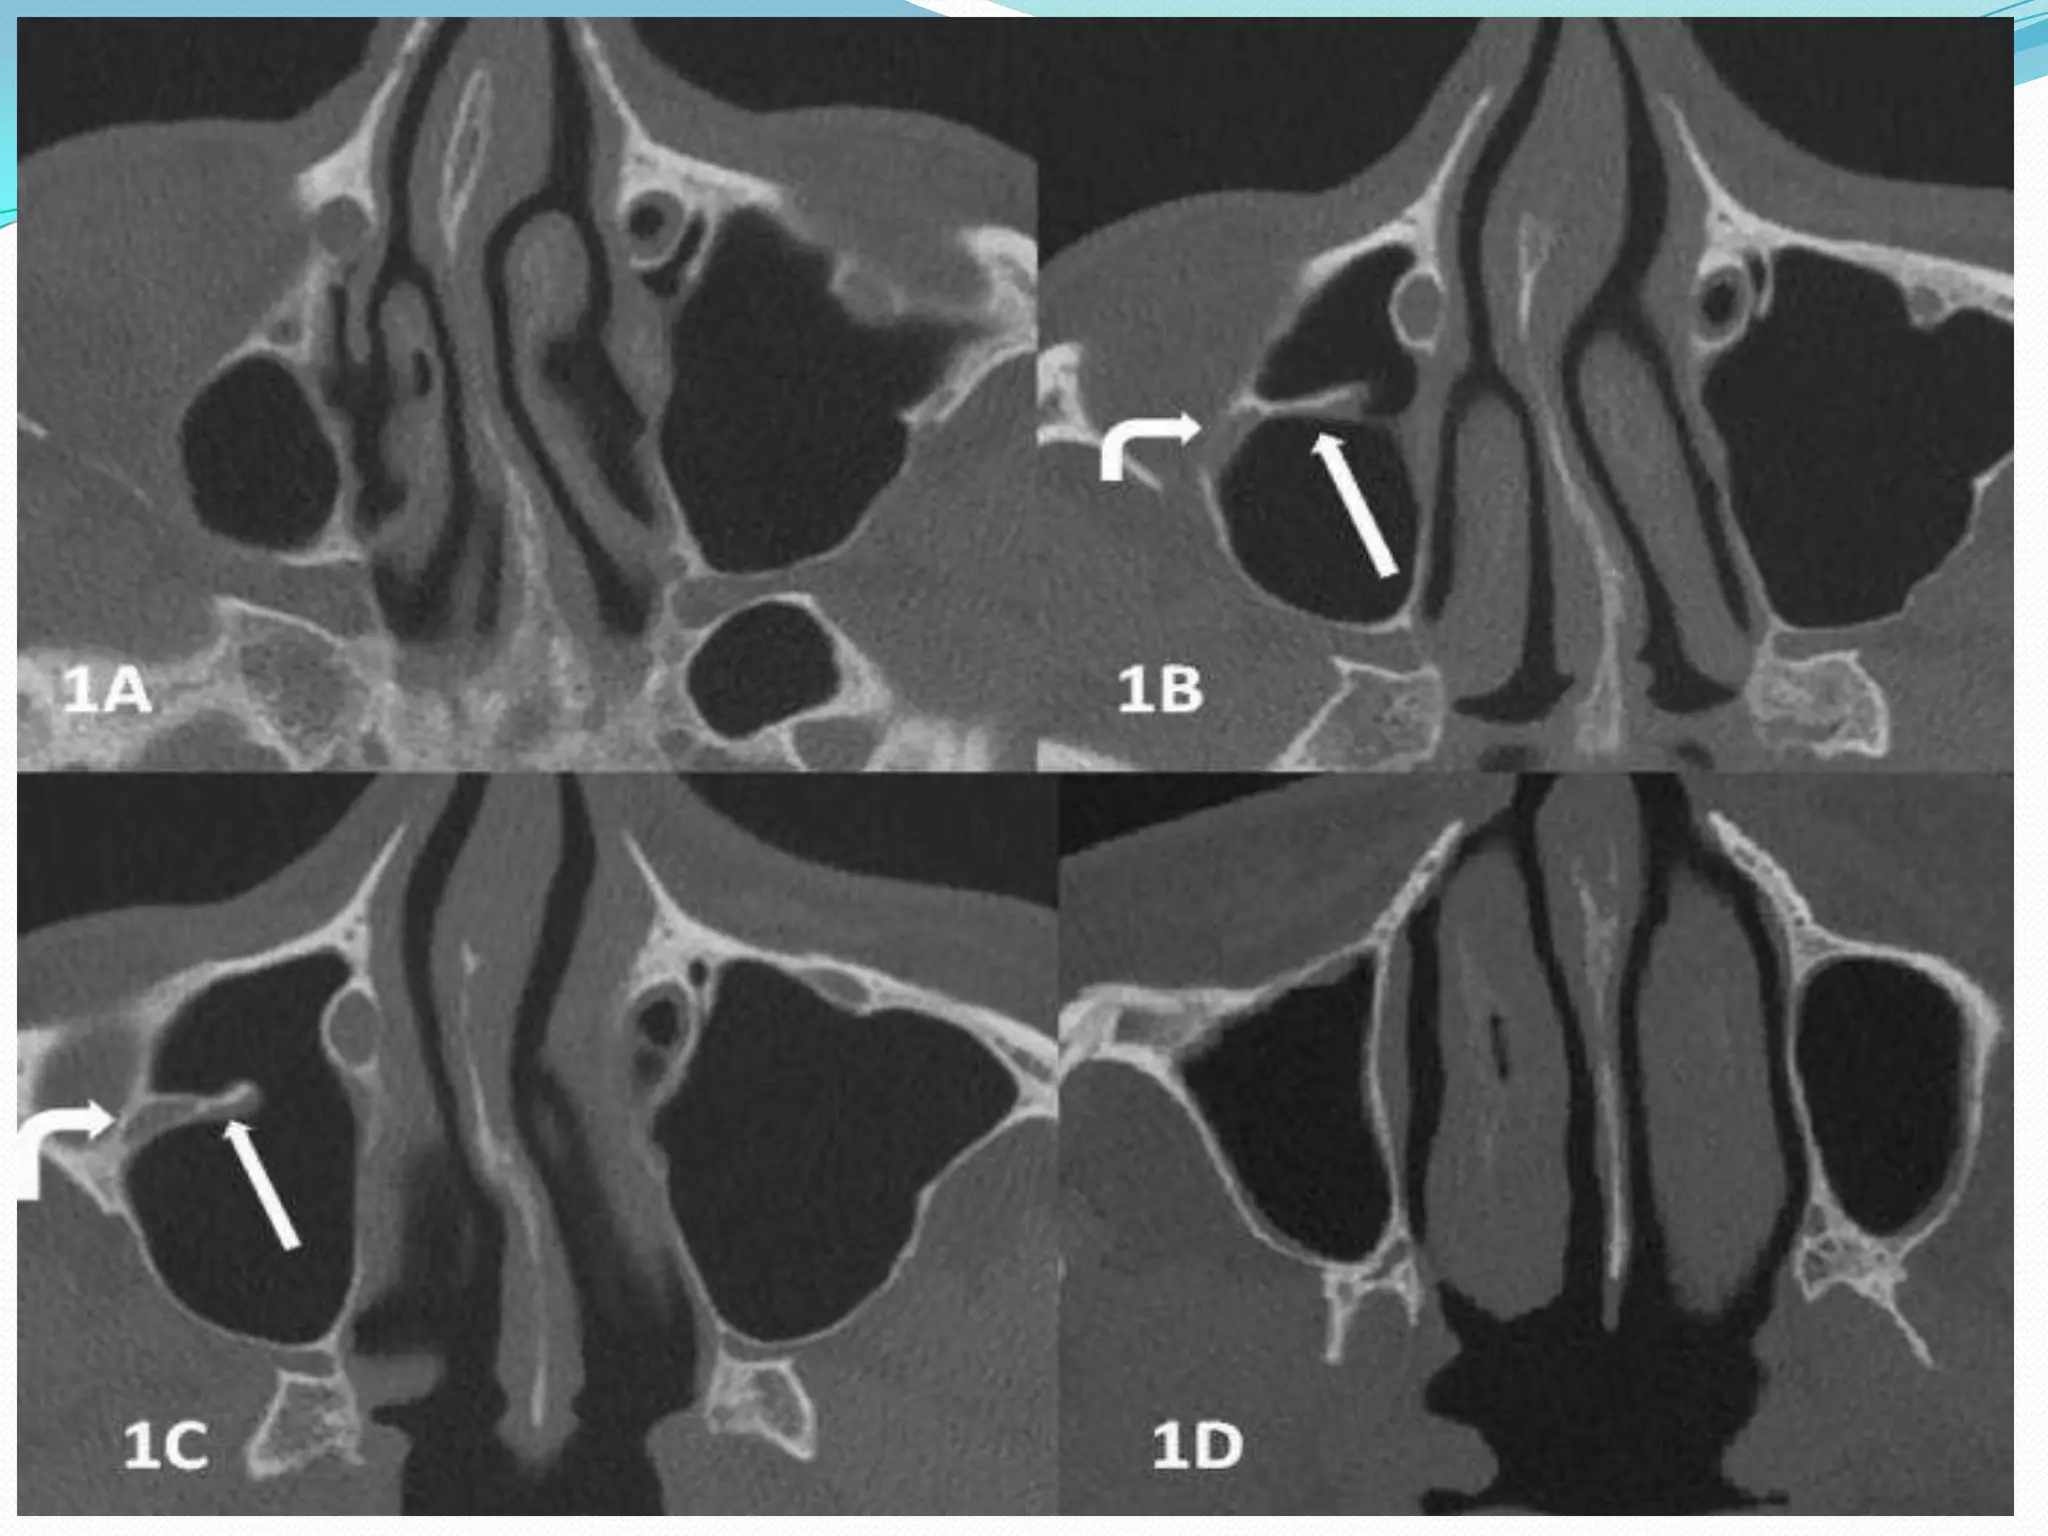

A, Axial unenhanced T1-weighted MR image shows

enlargement of right pterygopalatine fossa (asterisk).

Note

normal fat-filled left pterygopalatine fossa (arrow).

C, Coronal unenhanced T1-weighted MR image shows enlargeing

right maxillary nerve of intermediate signal intensity

(black arrow). Note tumor infiltration of right vidian canal (white

arrow).

G, Coronal CT scan (bone window) shows tumor in

pterygopalatine fossa (asterisk). Note enlarged maxillary

nerve groove (thick arrow) and normal left maxillary nerve (thin